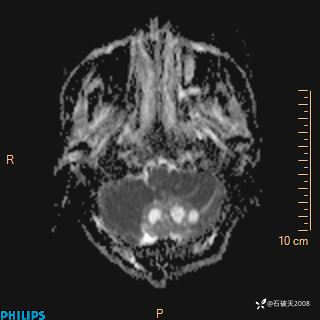

ADC